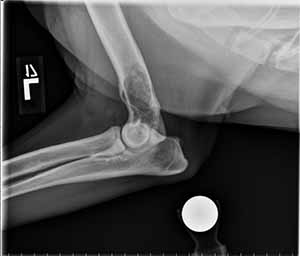

11-year-old dog with limp

Radiographs of the left elbow show the following:

Lateral view: